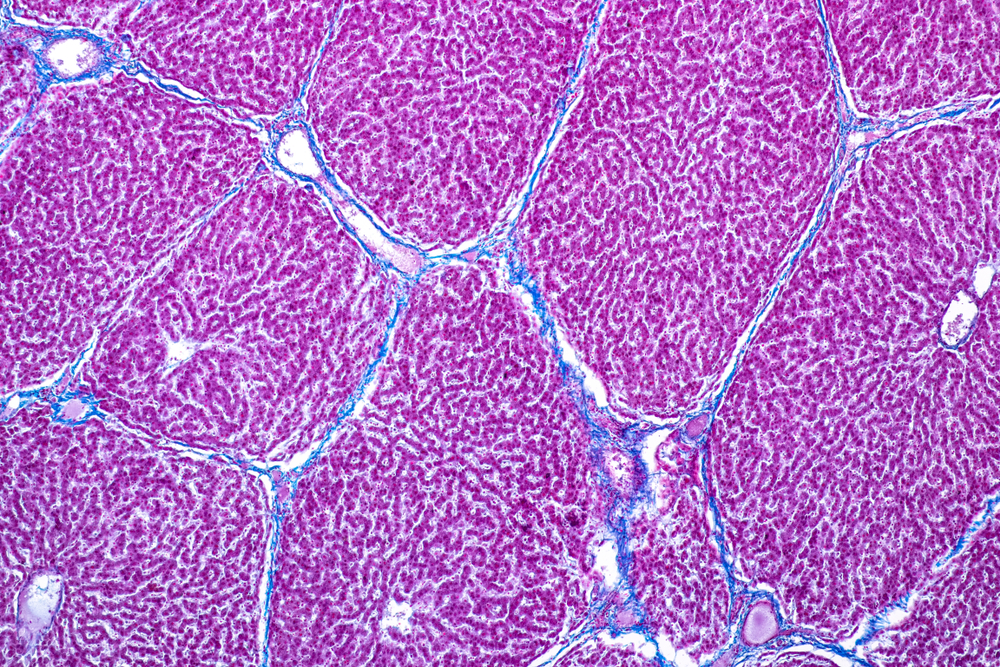

Structura țesutului hepatic

Țesutul hepatic este alcătuit în principal din hepatocite – celulele funcționale ale ficatului – care reprezintă aproximativ 80% din volumul organului. Acestea sunt organizate în lobuli hepatici, structuri care conțin vase de sânge, canale biliare și spații specializate pentru schimburile metabolice.

Mai exact, elementele principale ale țesutului hepatic sunt:

- hepatocitele, responsabile de majoritatea funcțiilor metabolice;

- sinusoidele hepatice, prin care circulă sângele și au loc procesele de filtrare;

- celulele Kupffer, cu rol imun în eliminarea toxinelor și microorganismelor;

- rețeaua de canale biliare, necesară transportului bilei;

- matricea extracelulară, care susține structura organului.

Structura compactă și organizarea în lobuli îi permit ficatului să proceseze rapid sângele care vine din tractul digestiv, să filtreze toxinele și să transforme nutrienții în compuși utili organismului. În funcție de sex și constituție, dimensiunile normale ale ficatului pot varia [1][2][3].